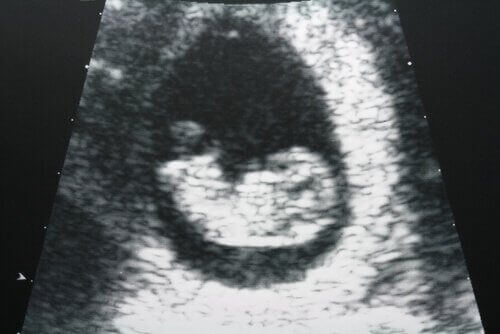

Ультразвукове дослідження також допоможе розпізнати можливі зміни у матці та яєчниках.